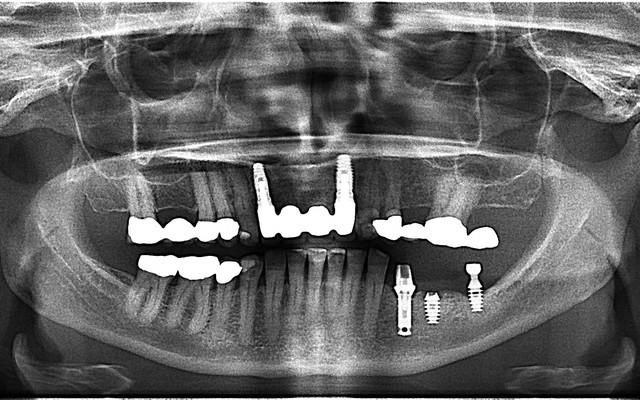

A panoramic radiograph is a panoramic scanning dental X-ray of the upper and lower jaw. It shows a two-dimensional view of a half-circle from ear to ear.

The X-rays use small amounts of radiation. Panoramic X-rays show a broad view of the jaws, teeth, sinuses, nasal area, and temporomandibular (jaw) joints. These X-rays show problems such as impacted teeth, bone abnormalities, cysts, solid growths (tumors), infections, and fractures

Dr Righardt van Huyssteen is a trusted dental practitioner based in Hermanus, offering general, aesthetic and restorative dentistry services in a modern and welcoming environment. His practice features cutting-edge technology, including a panoramic X-ray machine and an on-site dental laboratory, all...